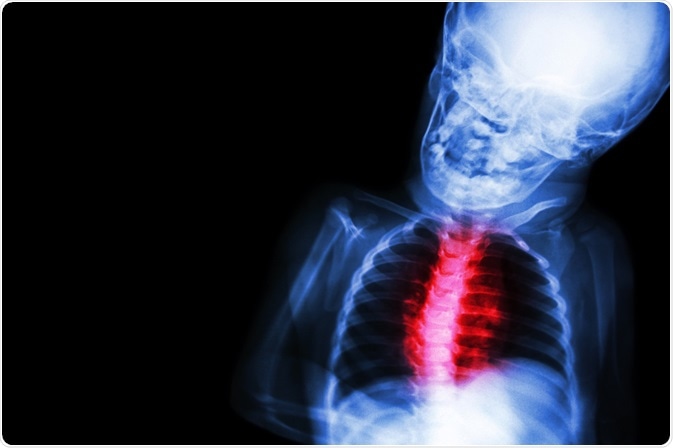

Congenital heart disease

Image Credit: Puwadol Jaturawutthichai/Shutterstock.com